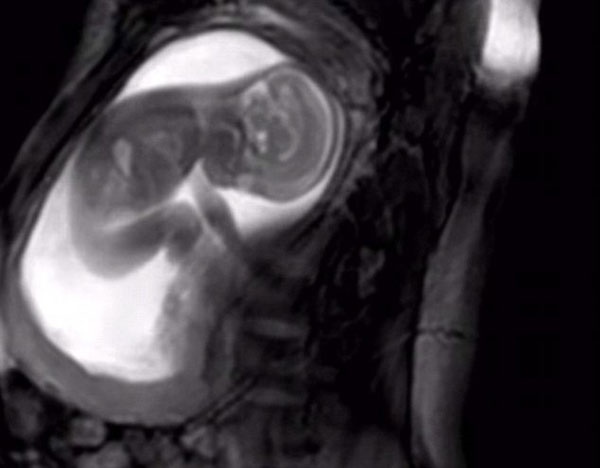

وی افزود: در وزارت بهداشت، سامانه خاصی بر اساس ماده ۵۴ قانون حمایت خانواده و جوانی جمعیت در حال طراحی است و درخواست غربالگری، فرآیند انجام آن، نتیجه تصویربرداری (سونوگرافی) و آزمایشات مربوط به غربالگری در این سامانه باید ثبت شود.

برکاتی این را هم گفت که نامه نگاری مذکور برای سطح یک ارائه خدمات و سامانههای مربوط به آن بوده است. بر اساس قانون، درخواست غربالگری آنومالیهای جنینی با عنایت به شرایط خاص آن در سطح یک ارائه خدمات بهداشتی قابل ارائه نیست و حتما درخواست غربالگری باید توسط متخصصین انجام شود و آیین نامه اجرایی نیز درهمین راستا تهیه شده است.